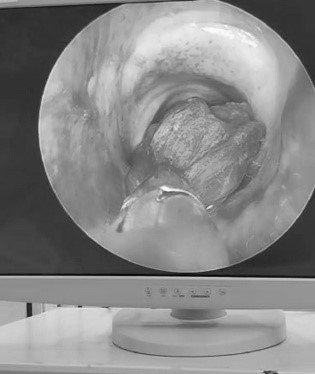

Se decidió la realización de una fibrobroncoscopía al pie de la cama, visualizando moldes endobronqueales hemáticos, los cuales obstruían de manera casi total el calibre de la vía aérea. Posterior a la realización del procedimiento, mejoró la ventilación y la oxigenación del paciente, este episodio vuelve a repetirse, por lo cuál se decidió procedimiento a través de fibrobronscopía rígida en quirófano. Se observa en Figura 1 la obstrucción generada en la vía aérea, y en la Figura 2 la extracción del molde.

Figura 2: Retiro endoscópico de molde